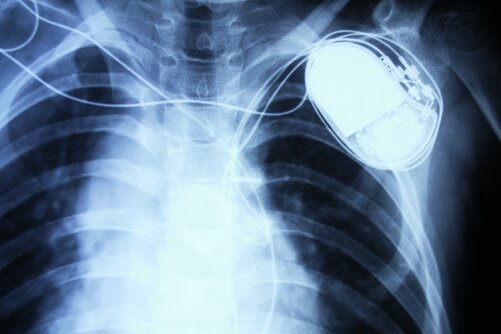

Auch Träger von Herzschrittmachern können umweltschonender fahren. Auch Träger von Herzschrittmachern können umweltschonender fahren. © iStock.com/Fodor90; fotolia/electriceye

Mit dem Schritt­macher ins Elektroauto – da kommen durchaus Befürchtungen zu Interferenzen auf. Unbegründet, sagt eine aktuelle Studie.

Ausbleibende Aktivierung, inadäquate Schocks oder Umprogrammierung: Das sind Komplikationen, die bei Trägern von Schrittmachern oder Defis in elektromagnetischen Feldern auftreten können. Elektroautos stellen aber wohl keine Gefahr dar, wie Forscher jetzt ermittelten.